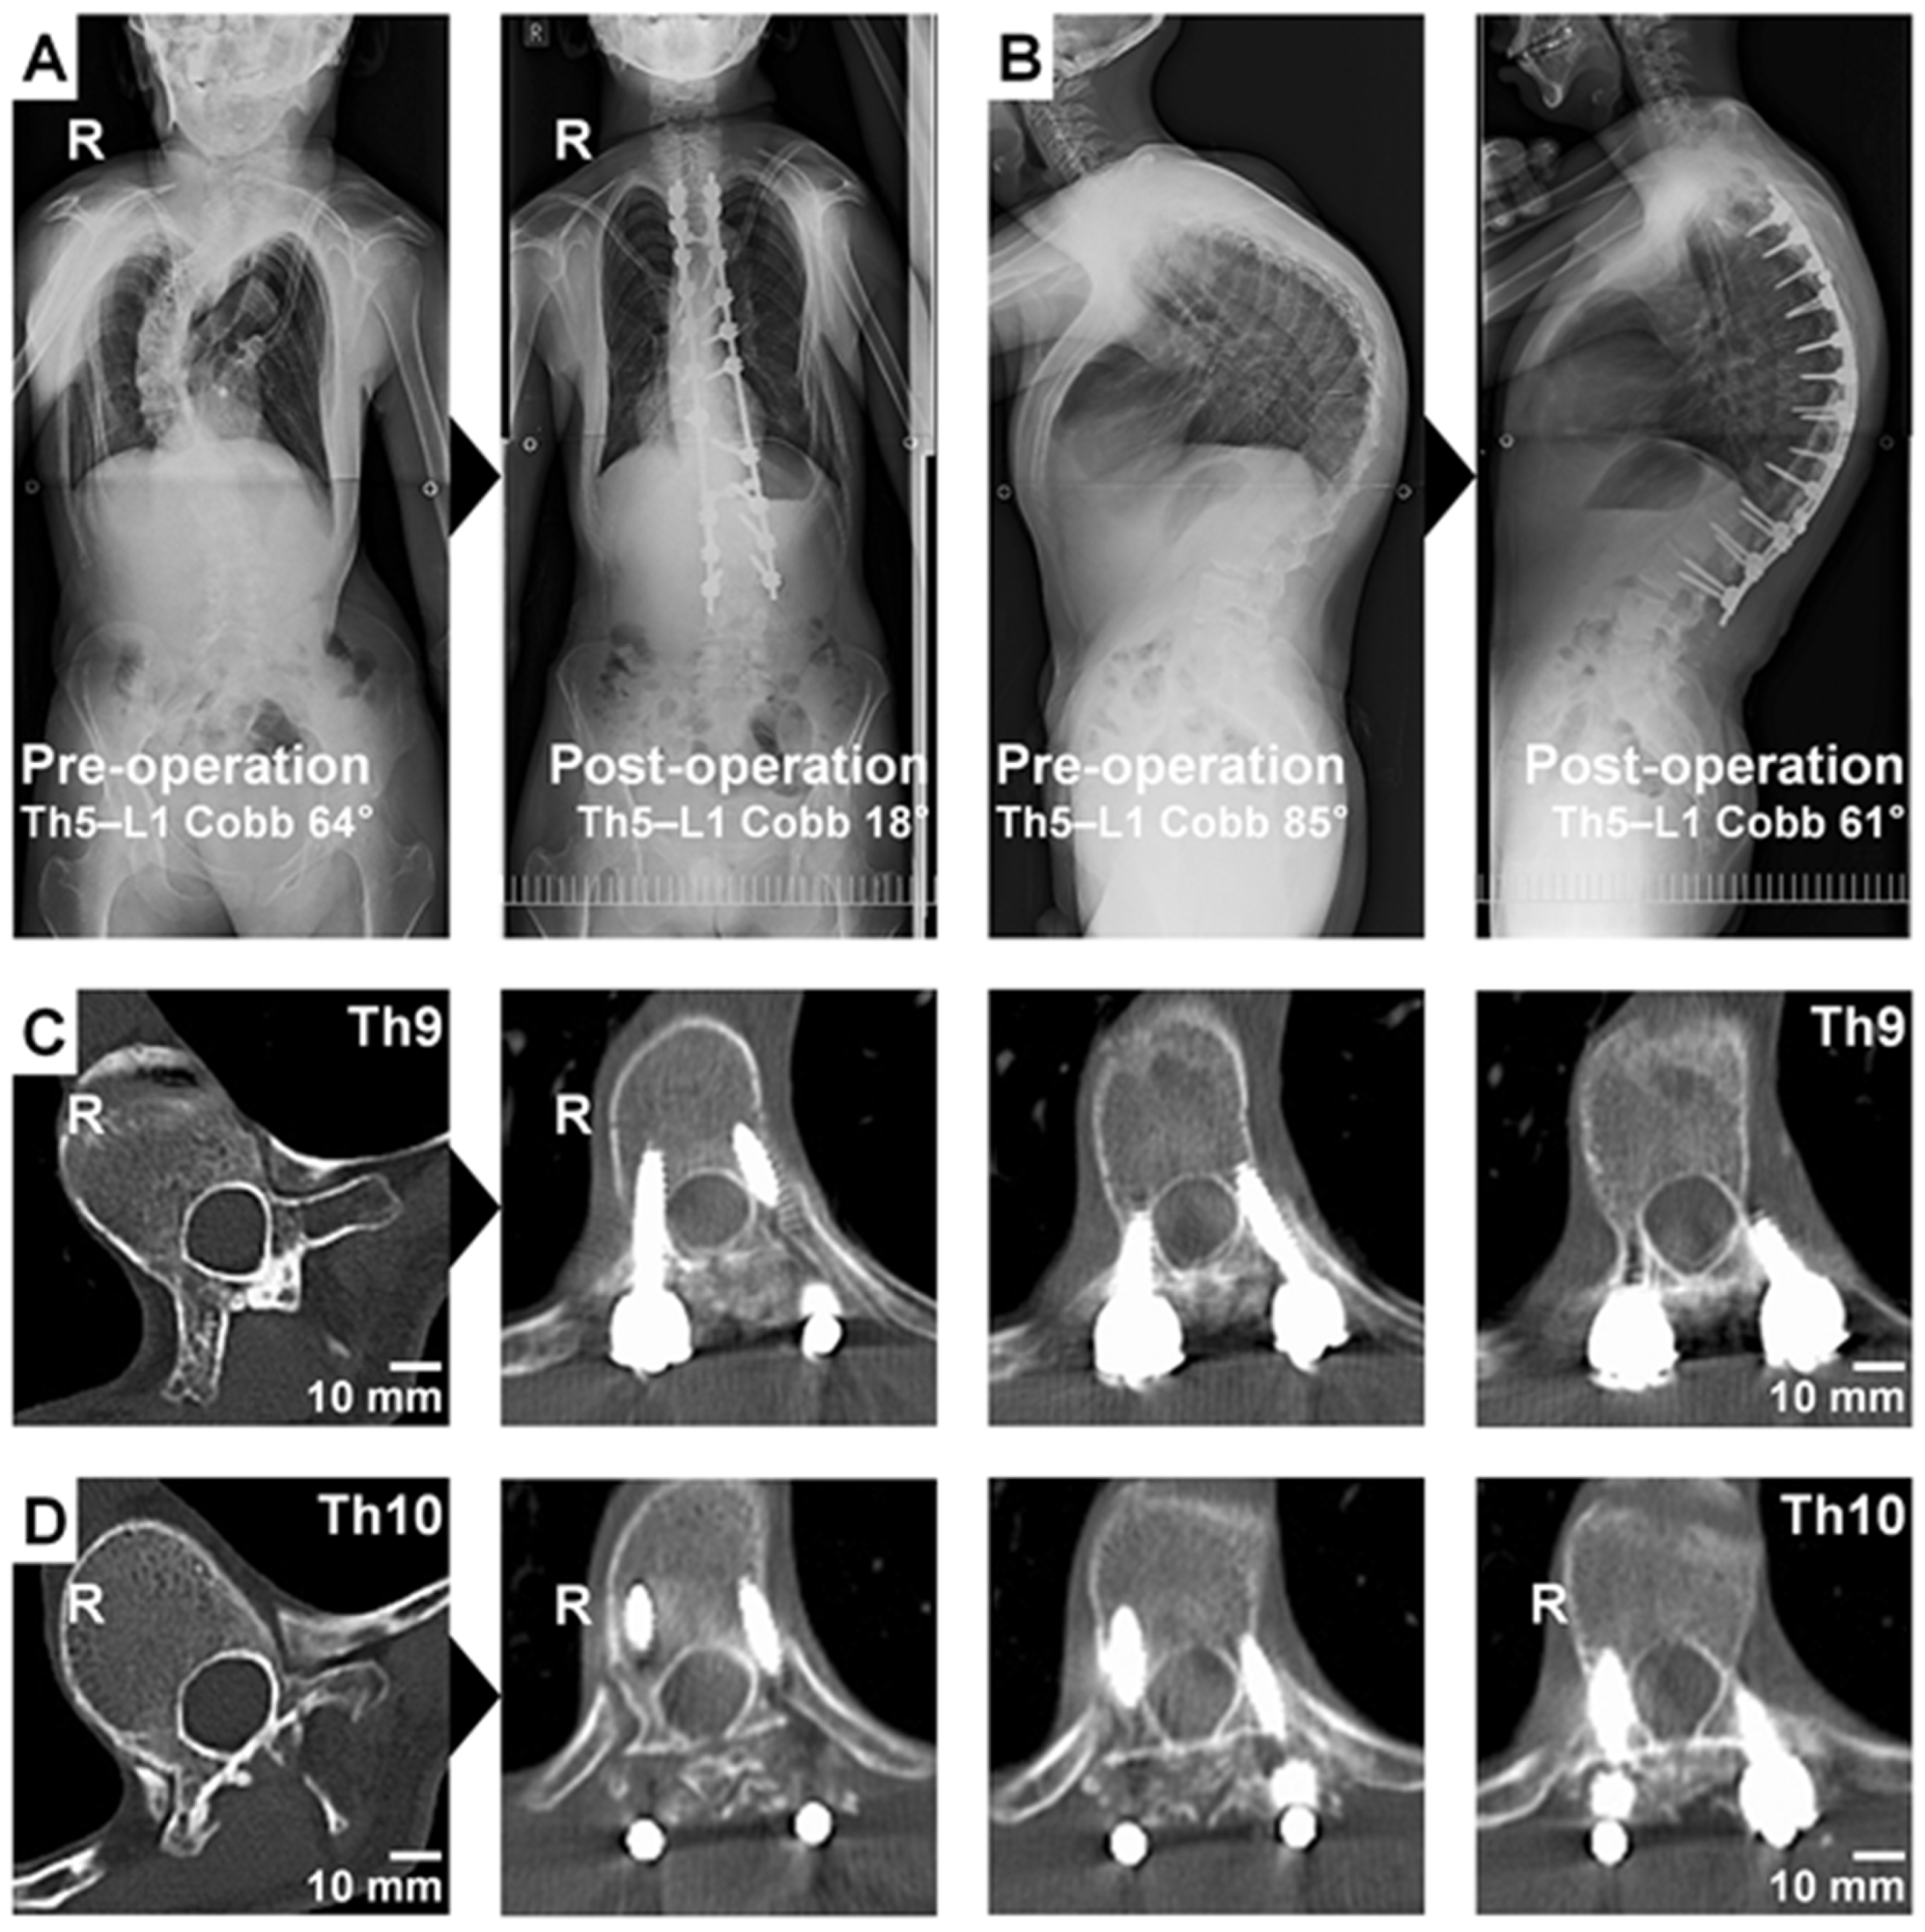

| Preoperative Cobb angle, mean ± SD [°] | 83.4 ± 26.0 | 82.3 ± 28.0 | 0.92 * |

| Postoperative Cobb angle, mean ± SD [°] | 41.8 ± 18.4 | 45.7 ± 23.4 | 0.67 * |

| Correction rate of the Cobb angle, mean ± SD [%] | 49.7 ± 18.3 | 46.5 ± 18.6 | 0.70 * |